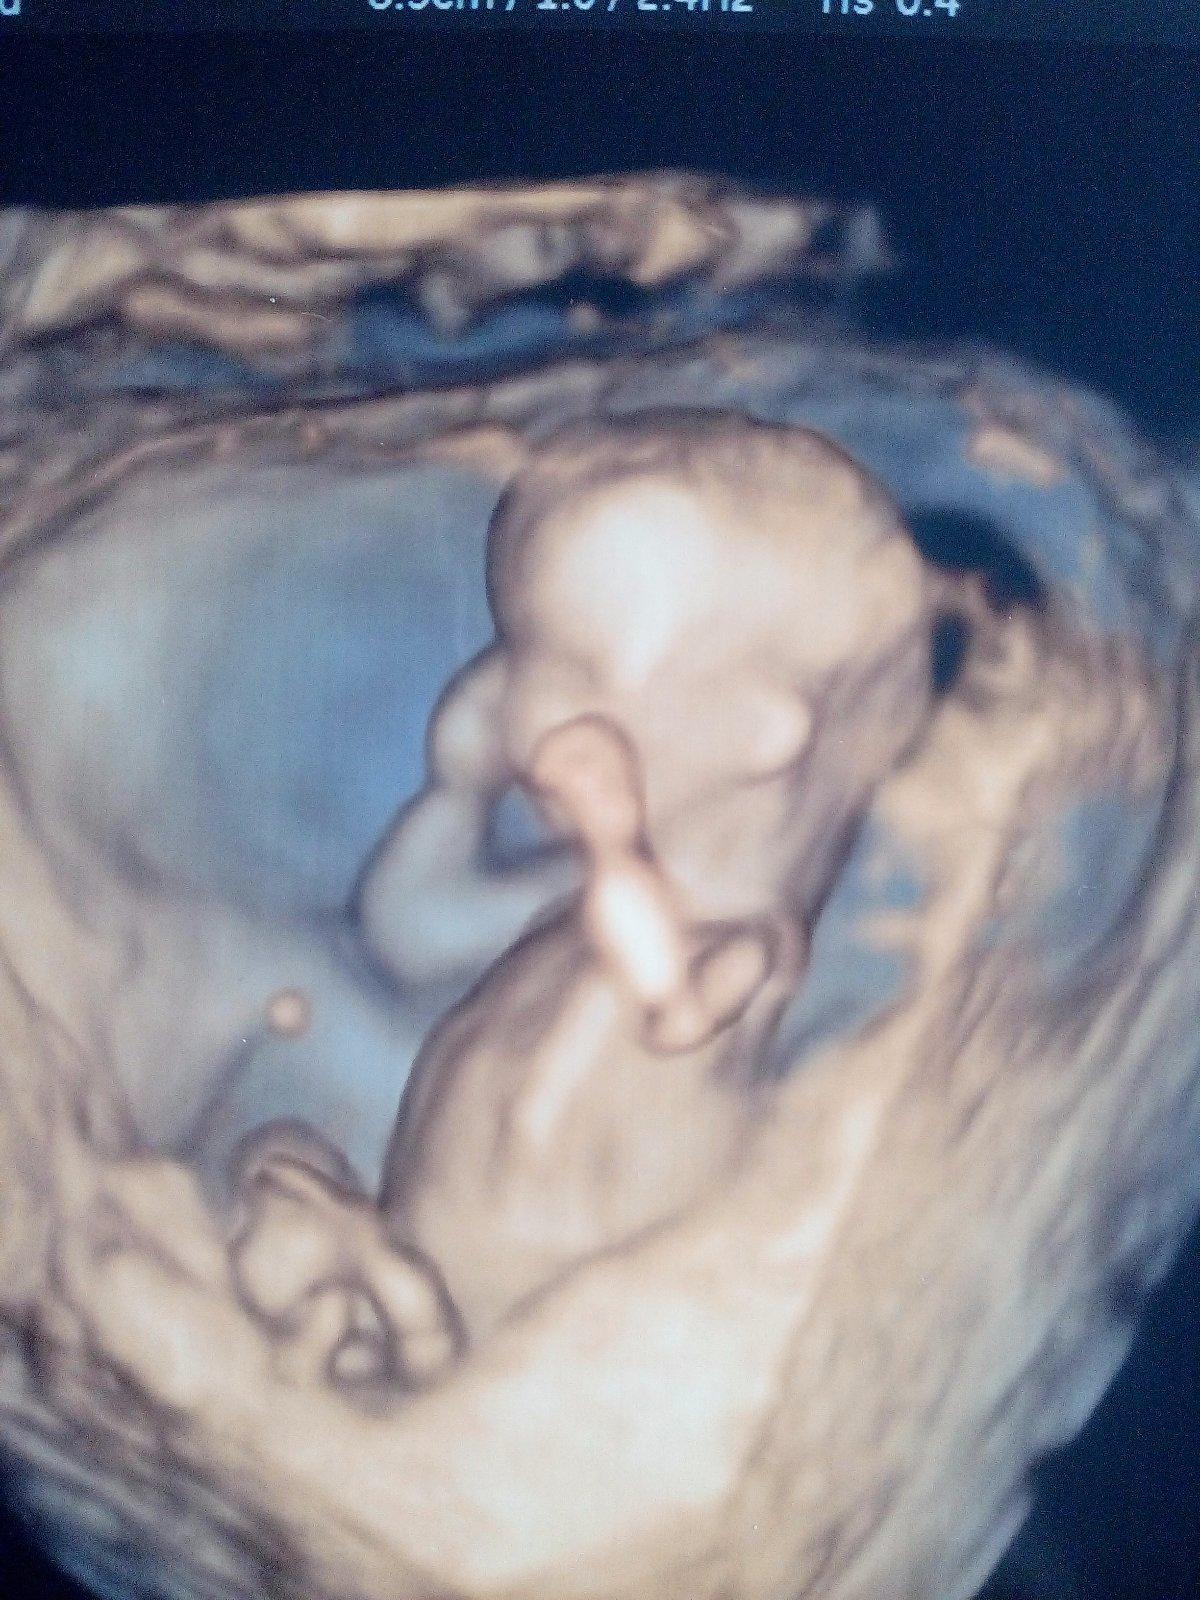

@denidi nezmylila si si to lebo prvotrimestralny skrining ma 2 casti.. meranie NT cize ultrazvuk a potom biochemicky skrining cize odber krvi,ale krv neberie kazdy lekar..niektori beru niektori nie.. a dokopy sa to vola kombinovany skrining.. ja byvam az za Nitrou,Martin mam tak 150 km asi

@denidi ano minuly tyzden mi brali krv,cakam na vysledky.. sestricka nevola ked su dobre vysledky tak dufam ze nebude volat :D ale keby boli zle vysledky tak neviem co by som spravila..amnio je najpresnejsia takze... ale zas na druhej strane je tam riziko potratu a pri trisomy a prenascnae nie..Vsetko bude ok,musi :D

Baby ktoré ste boli u Grochala na prvotrimestralny screening,bral vám aj krv,alebo robil len ten screening?